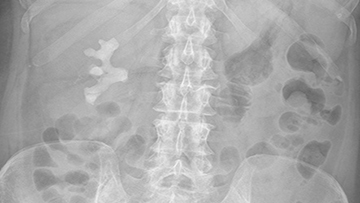

0:07:57.8 RW: And when you look at one, it looks like, deer antlers, a staghorn. I found a spectacular x-ray of a staghorn calculus on Wikimedia that you can see in our show notes today. Or if you happen to have the seventh edition of my book, you can see a photograph of a whole kidney that has been removed because it was taken over by this enormous stone on page 487. And this is probably the procedure that our client is about to go through. What makes stag horn calculi so different from other kidney stones? Well, in the United States at least, the main issue is what the stones are made of. Staghorn calculi are not usually made of the calcium oxalate or calcium phosphate that we see with other stones. Instead, they are made mostly of a substance called Struvite, which is to say magnesium ammonium phosphate. And there's a whole story which involves bat guano about how Struvite got its name. I will spare you the details.